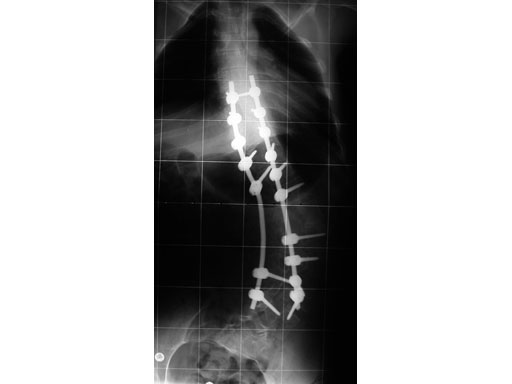

A 23-year-old man with neurogenic kyphoscoliosis, Cobb angle: 120. Fusion of T7S1 with universal reduction screws. Duration of surgery: 4.5 hours.